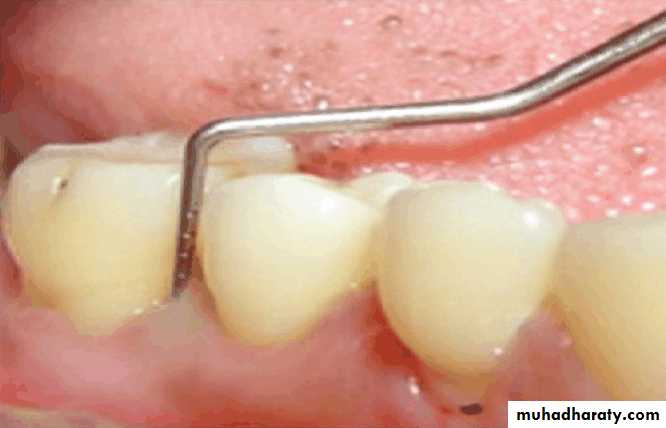

Periodontal examination that includes

Determination of pocket depth, examination for evidence of infection or inflammation, the amount of attached gingiva of the prospective abutment teeth is madeThe oral mucosa is examined visually and with palpation for evidence of pathologic change

The examination is made for the presence of tori, exostoses, sharp or prominent bony areas , soft or hard tissue undercuts, enlarged tuberosities.

Evaluation of periodontium

Periodontal disease is one of the main etiologic factors in the loss of the teethA removable partial denture placed in the presence of active periodontal disease will contribute significantly to the rapid progression of the disease and the loss of the remaining teeth.

The causative factors must be eliminated, the disease process must be controlled before the fabrication of the prosthesis.

Examination findings that indicate possible need for periodontal treatment include

Pocket depth in excess of 3 mmFurcation involvement

Deviations from normal color and contour in gingiva, indicating gingivitisMarginal exudate

Potential abutment teeth with less than 2 mm of attached gingiva